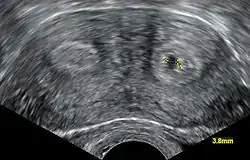

L'échographie utérine est utile à la recherche des causes utérines car celles-ci sont fréquentes et parfois curables. L'échographie, quand elle est orientée, est très performante pour établir un diagnostic différentiel entre utérus cloisonné et bicorne même si l'hystérographie reste la référence dans beaucoup d'autres situations (unicorne, béance, hypoplasie, DES syndrome).